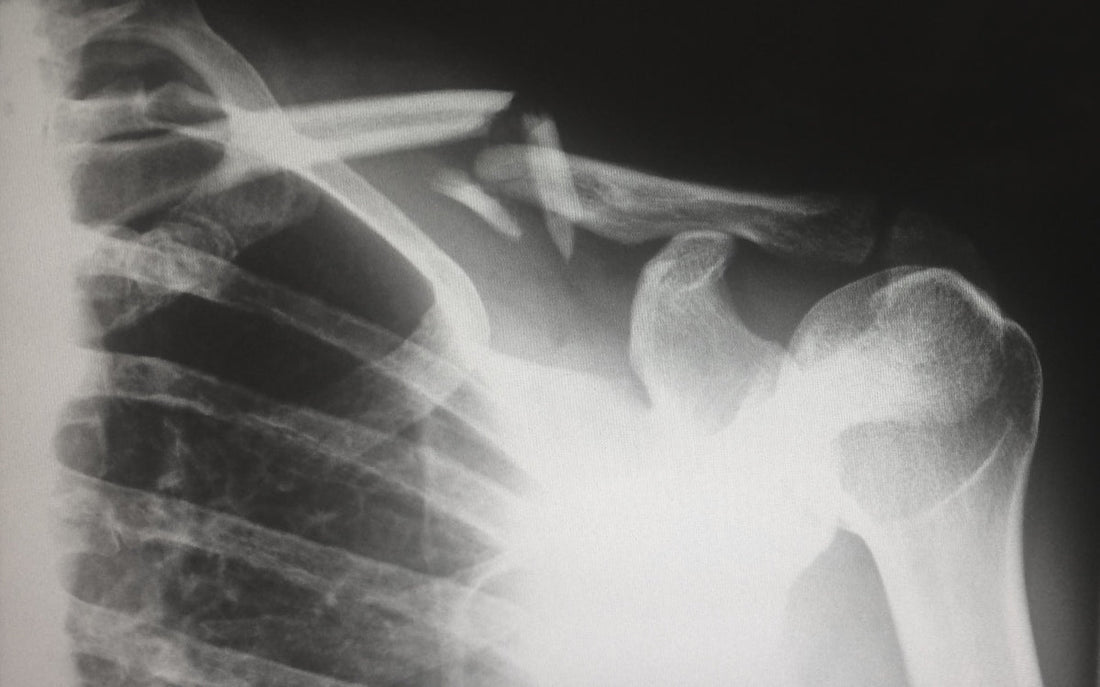

هشاشة العظام، أو ما يُعرف بمرض هشاشة العظام، هو اضطراب وراثي يتميز بهشاشة العظام وسهولة كسرها، وغالبًا ما يكون ذلك دون سبب واضح أو معدوم. وتتعدد أشكال هذه الحالة، من خفيفة إلى شديدة، وقد تؤثر بشكل كبير على نمط حياة الفرد وقدرته على الحركة.

يحدث ترقق العظم نتيجة طفرات في الجينات المسؤولة عن إنتاج الكولاجين، وهو بروتين أساسي في أنسجة العظام يُعطي القوة والبنية. تشمل الأعراض الأكثر شيوعًا لمرض ترقق العظم الناقص كسور العظام المتكررة، وازرقاق الصلبة (الجزء الأبيض من العينين)، وفقدان السمع، وضعف نمو الأسنان، وارتخاء المفاصل. في الحالات الشديدة، قد يُعاني الأفراد من تقزم النمو أو تشوه شكل الجمجمة، ويواجهون تحديات خاصة تتعلق بالحركة والاستقلالية.

- النوع الثالث: شكل حاد من هشاشة العظام، حيث يواجه الأفراد العديد من الكسور، مما يؤدي إلى تشوه العظام التدريجي بمرور الوقت.